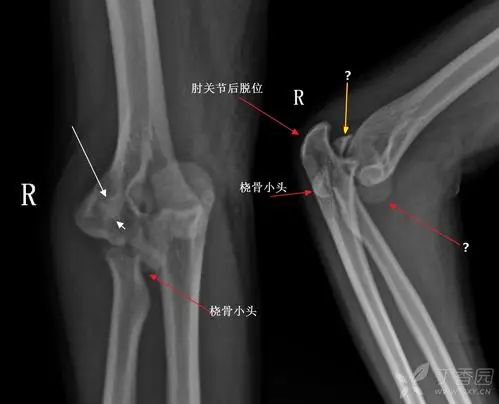

桡骨小头脱位,请求治疗方案